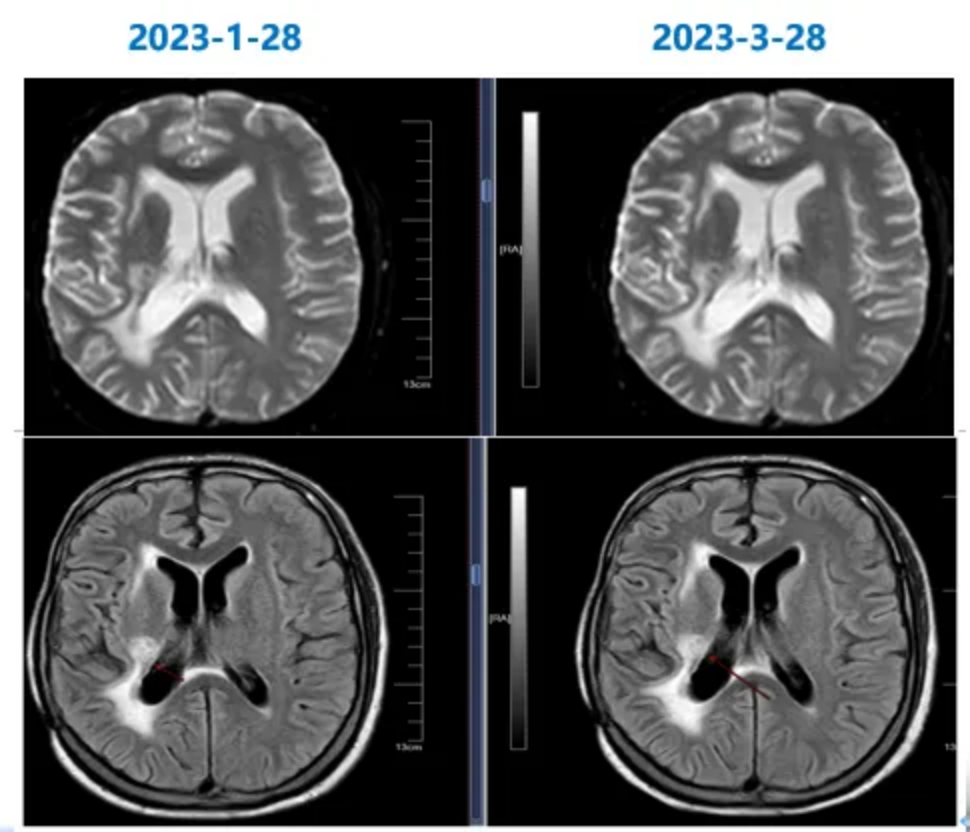

2021-2-2行一线治疗:放疗方案:CTV1(术后瘤床),60Gy/30f(图3)。放疗期间同步口服替莫唑胺140mg qd/42d,放疗后一月开始替莫唑胺辅助治疗。

图3 放疗计划

2023-3-28至2023-4-13脑部再程放疗:采用调强适形放疗(IMRT)。GTV(脑肿瘤灶):35Gy/10f,CTV(GTV周围亚临床病灶) 30Gy/10f。每天1次,2周完成(图6)。

图5 放疗计划